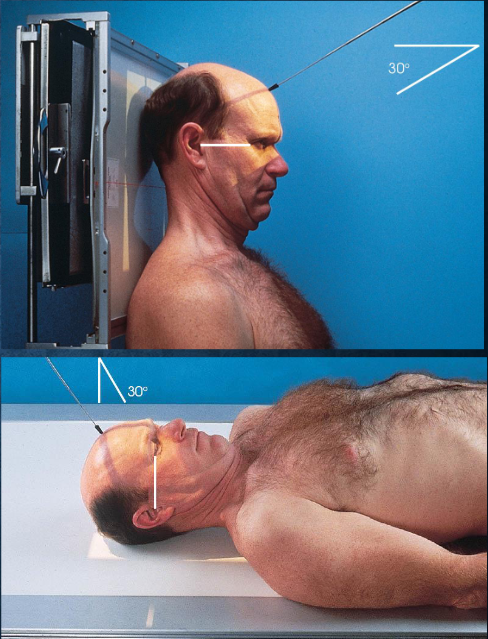

AP axial (Towne) skull

patient and part position:

supine or upright, seated

MSP centered to midline

MSP perpendicular

OML perpendicular to IR

IOML perpendicular if patient cannot flex neck enough

top border of IR level with vertex

IR centered at or near foramen magnum

respiration suspended

CR:

directed through foramen magnum

OML: 30 degrees cacudal

IOML: 37 degrees caudal

collimation:

1 inch beyond the skin line of the skull

AP axial (Towne) skull image criteria

no rotation:

equal distance from lateral border of skull to lateral margin of foramen magnum

symmetric petrous ridges

dorsum sellae and posterior clinoid process visible within foramen magnum

penetration of occipital bone without excessive density at parietals